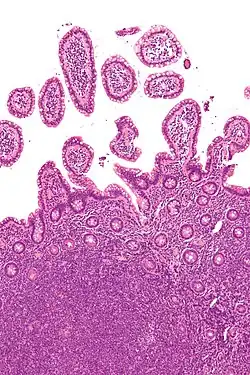

| Micrograph showing mantle cell lymphoma (bottom of image) in a biopsy of the terminal ileum. H&E stain. | |

The history and physical examination may reveal some of the signs and symptoms consistent with Mantle Cell Lymphoma. Biopsy of the involved tissues (such as the lymph nodes, bone marrow, gastrointestinal tract, spleen or other areas) shows the characteristic histopathologic changes of MCL. There are distinct growth patterns of MCL seen on biopsy; these include the diffuse type, nodular type, mantle zone lymphoma and in situ mantle cell lymphoma.[8] In the diffuse growth pattern, there is a diffuse growth of lymphoma cells throughout the lymph node resulting in effacement of the architecture of the lymph node.[8] In the nodular type, there are large nodules of MCL cells in the lymph node with no germinal centers observed.[8] In MCL with expansion of the mantle zone, the lymphoma cells cause expansion of the mantle zone around normal germinal centers.[8] And in MCL in situ, the lymphoma cells are contained within the mantle zone without expansion.[8] Histologically, the lymphoma cells in classic MCL are characterized as small to medium lymphocytes with scant cytoplasm and clumped chromatin with prominent nuclear clefts and the nucleoli are not visible.[8] There are cytologic subtypes; the blastoid subtype, is characterized by round nuclei, fine chromatin with some distinct nucleoli.[8] The pleomorphic subtype is characterized by nuclei that vary in size and shape with some having a cleaved form.[8] The blastoid and pleomorphic subtypes of MCL are associated with a more aggressive course.[8]